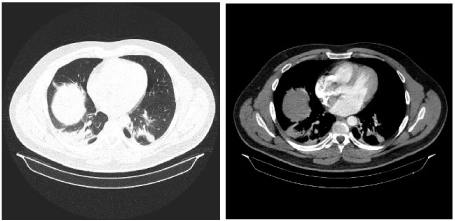

In the framework of this article we present the case of a man age 33, nonsmoker, without exposure to respiratory hazards, former professional rugby player, without a significant past medical or family history , without treatment at that time, which had presented in our medical service for hemoptysis in  small quantity, that began a month and a half before that moment , when he discharged about 50 ml of blood, the next episode of hemoptysis occurred during the day in which he presented at the hospital with a discharge of about 60 ml of blood. Whilst questioning the patient about other symptoms we found out the approximately a year ago the patient observed an increase in the volume of his right calf associated with pain, redness,  an increase of local temperature, all of which resolved spontaneously within the next few days. It is important to remark that at moment of admission the patient denied chest pain, fever, dyspnea, arthralgia, rashes, bruises or weight loss. Furthermore we must specifically mention that the patient does not have a history of chronic pulmonary disease, immunosuppressive therapy or proximity to known tuberculosis patients. The physical examination at the time of the hospitalization did not reveal any notable elements. The complete blood count and biochemistry tests showed a biological inflammatory syndrome without leukocytosis; it is worth mentioning that multiple tests of the D-dimers were negative.  A first tomographic examination showed a pulmonary consolidation process in the right inferior lobe with air bronchogram sign and minimal bilateral pleural fluid accumulation (Figure 1). A second tomographic examination, preformed 7 days later, revealed bilateral pulmonary consolidation with the same characteristics as the previous observed consolidation (Figure 2). Through serial bronchoscopic examinations, an evolution of the lesions was observed, at the first examination we observed rare bilateral anthracotic spots and an active hemorrhagic source at the level of the right basal pyramid (the precise source of the bleeding was not identified, just that the source could be a intersegmentary carina and consequently the hypothesis of broncho-vascular fistula arouse), no other notable elements were identified. The latter bronchoscopic examination recorded the cessation of the bleeding (under the hemostatic effect of the medication), and without the constant stream of blood we identified an area of vascular ectasic hyperplasia at the right anterobazal carina. A hematology consult revealed a hereditary thrombophilia thru a mutation of the MTHFR gene - methyl tetrahididrofolat reductase (C677 mutation T A1298C- heterozygous genotype) and the mutation of the second coagulation factor - prothrombin  - heterozygous genotype.

Figure 2. A second tomographic examination, preformed 7 days later, revealed bilateral pulmonary consolidation with the same characteristics as the previous observed consolidation